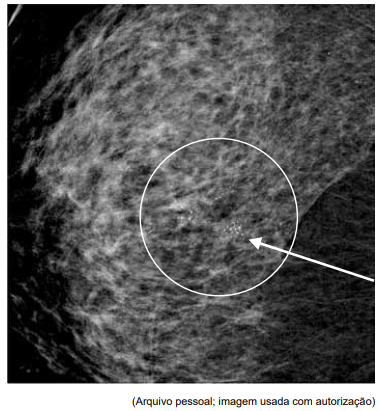

Paciente de 57 anos, assintomática, sem história familiar

de câncer de mama, comparece ao serviço de ginecologia trazendo mamografia de rastreamento, reproduzida a

seguir. O exame físico não evidencia nódulos palpáveis

ou linfadenopatia axilar.

Qual a conduta diagnóstica mais apropriada neste caso e a hipótese histopatológica mais provável, caso se confirme malignidade?